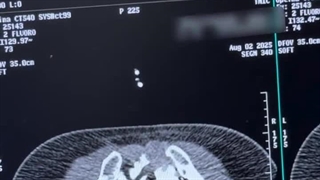

تزریق سیمان در مهره کمر ۰۱:۳۵

تزریق سیمان در مهره کمر